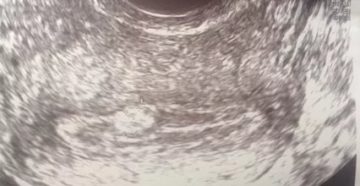

Неразвивающаяся беременность: профилактика неудачного зачатия Радость от осознания наступившего счастья может омрачить печальное событие: неразвивающаяся…